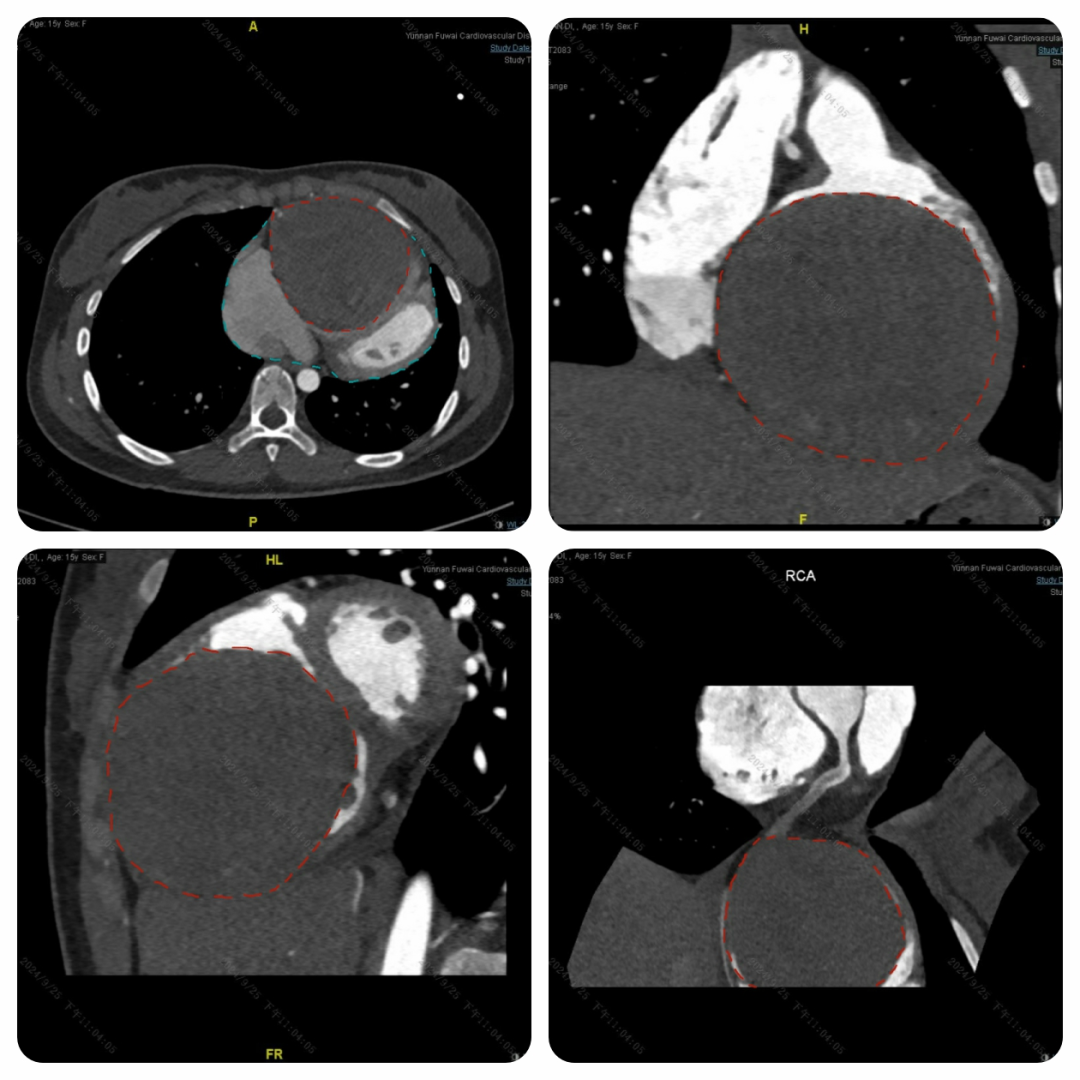

15 岁,本应是充满活力、肆意奔跑在青春赛道上的年纪,小迪(化名)却被胸口的憋闷与疲乏无情笼罩。两年间,这种不适如影随形,且愈发严重。在老家医院初步判断为心脏病后,心急如焚的家人带着小迪辗转来到云南省阜外心血管病医院(以下简称:云南省阜外医院)经过一系列全面的心脏检查,一个惊人的发现让所有人都捏了一把汗 —— 小迪的心脏上竟长出了一个犹如 “大炸弹” 般的东西。

随着心脏超声、心脏 CT、心脏核磁以及冠状动脉造影检查结果的陆续出炉,答案终于浮出水面:它源自小迪的右冠状动脉。

这颗 “炸弹” 就像一个贪婪的 “侵略者”,当发现它时,其直径已将近 10 公分,源源不断的血液从右冠状动脉涌入其中,持续压迫着心脏,小迪也因此愈发难受。冠状动脉上出现如此巨大的 “炸弹”,极为罕见。一旦这个 “炸弹” 哪天突然 “爆炸”,小迪年轻的生命将岌岌可危。

发现情况如此危急,云南省阜外医院医护团队迅速行动起来,开启了紧张的 “扫雷” 行动,通过心脏外科手术,成功拆除了这颗危及生命的 “大炸弹”。如今,18 岁的小迪已完全康复,能和同龄人一样尽情享受生活、投入工作,绽放属于她的青春光彩。